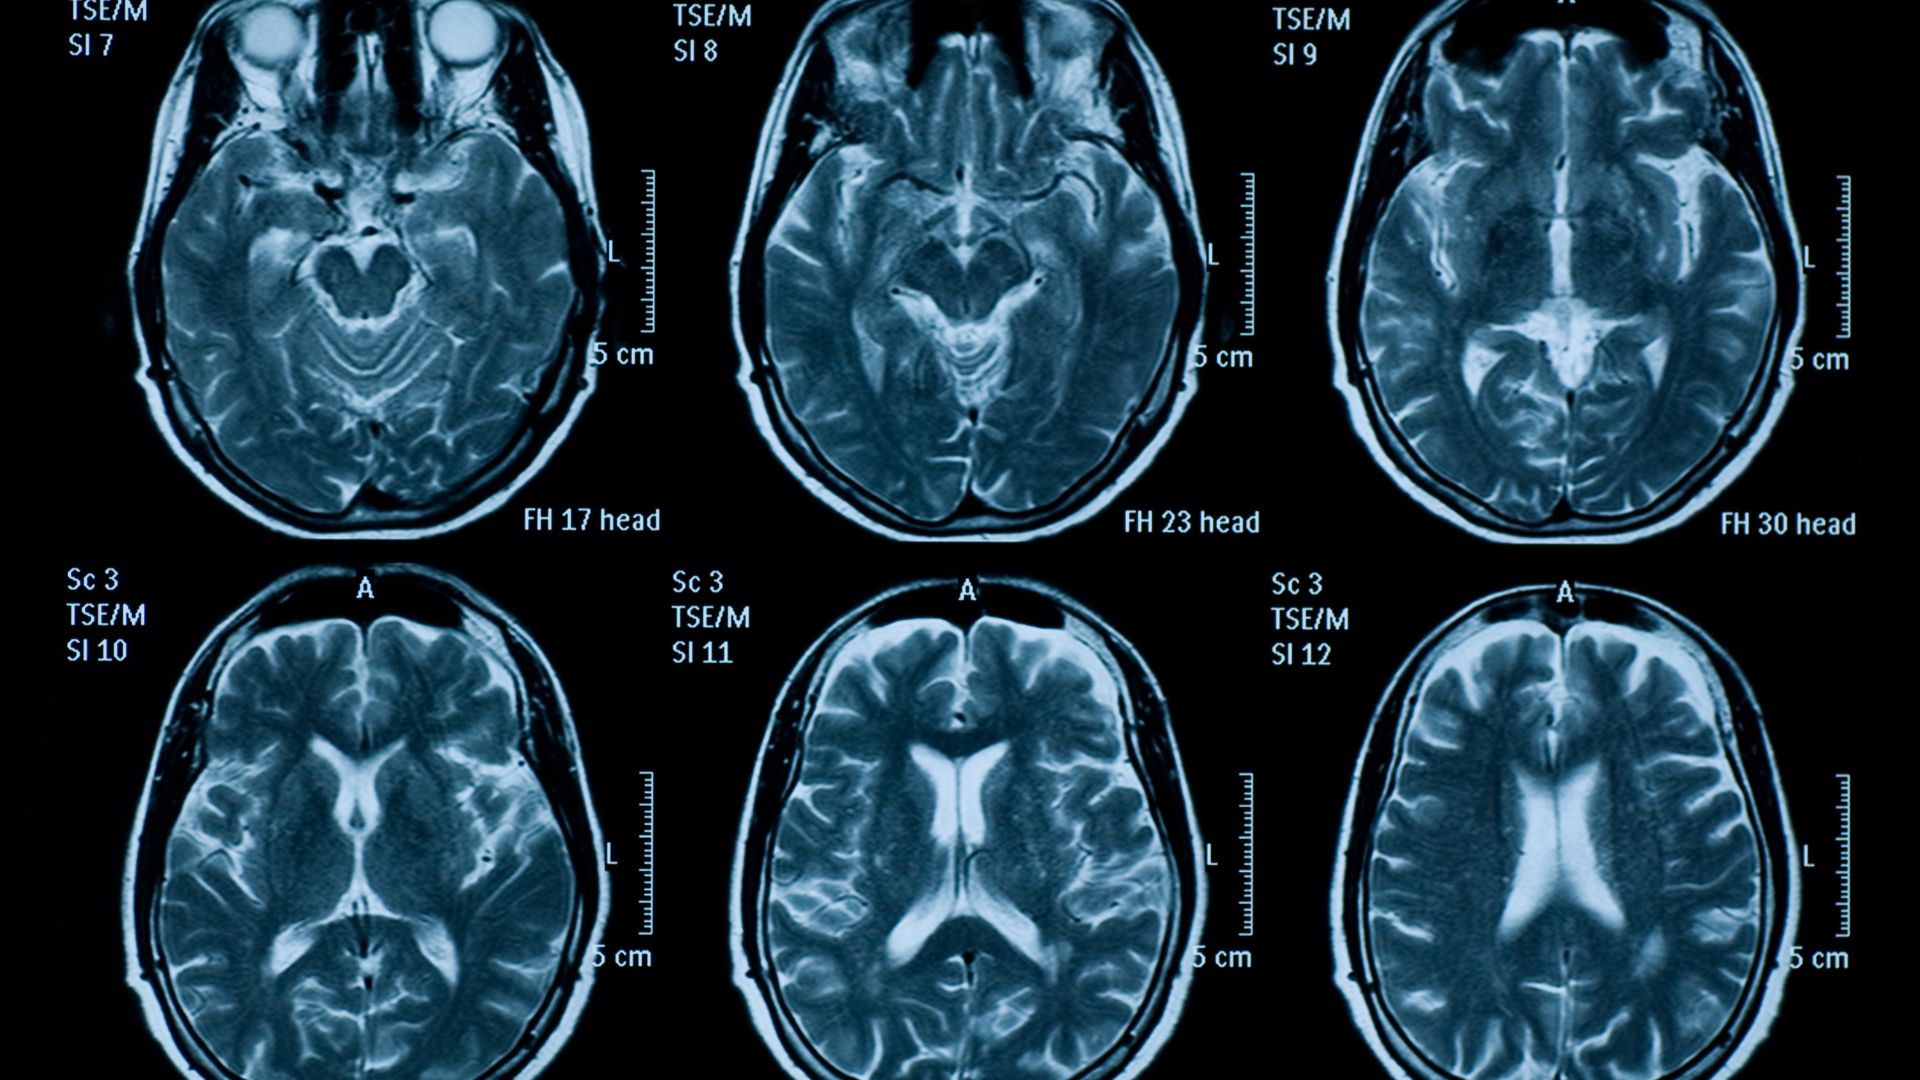

Chụp cộng hưởng từ não (MRI não) là kỹ thuật chẩn đoán hình ảnh hiện đại, cho phép quan sát chi tiết cấu trúc não bộ mà không cần can thiệp xâm lấn. Phương pháp này thường được chỉ định khi nghi ngờ các vấn đề như tai biến mạch máu não, u não, tổn thương thần kinh hoặc đau đầu kéo dài không rõ nguyên nhân. Tuy nhiên, do chi phí cao hơn so với chụp CT hay X-quang, nhiều người băn khoăn về mức giá cũng như các khoản phát sinh có thể gặp. Việc nắm rõ thông tin trước khi thực hiện sẽ giúp người bệnh chuẩn bị tốt hơn về tài chính và tâm lý.

So với chụp CT hay X-quang, MRI não có ưu thế vượt trội trong việc đánh giá mô mềm và cấu trúc thần kinh. Phương pháp này không sử dụng tia xạ, do đó an toàn hơn khi cần chụp nhiều lần.

Chính nhờ độ chính xác cao, MRI não thường được ưu tiên trong các trường hợp cần chẩn đoán chi tiết, dù chi phí có thể cao hơn. Đây cũng là lý do nhiều người tìm hiểu kỹ giá chụp MRI não trước khi quyết định thực hiện kỹ thuật này.